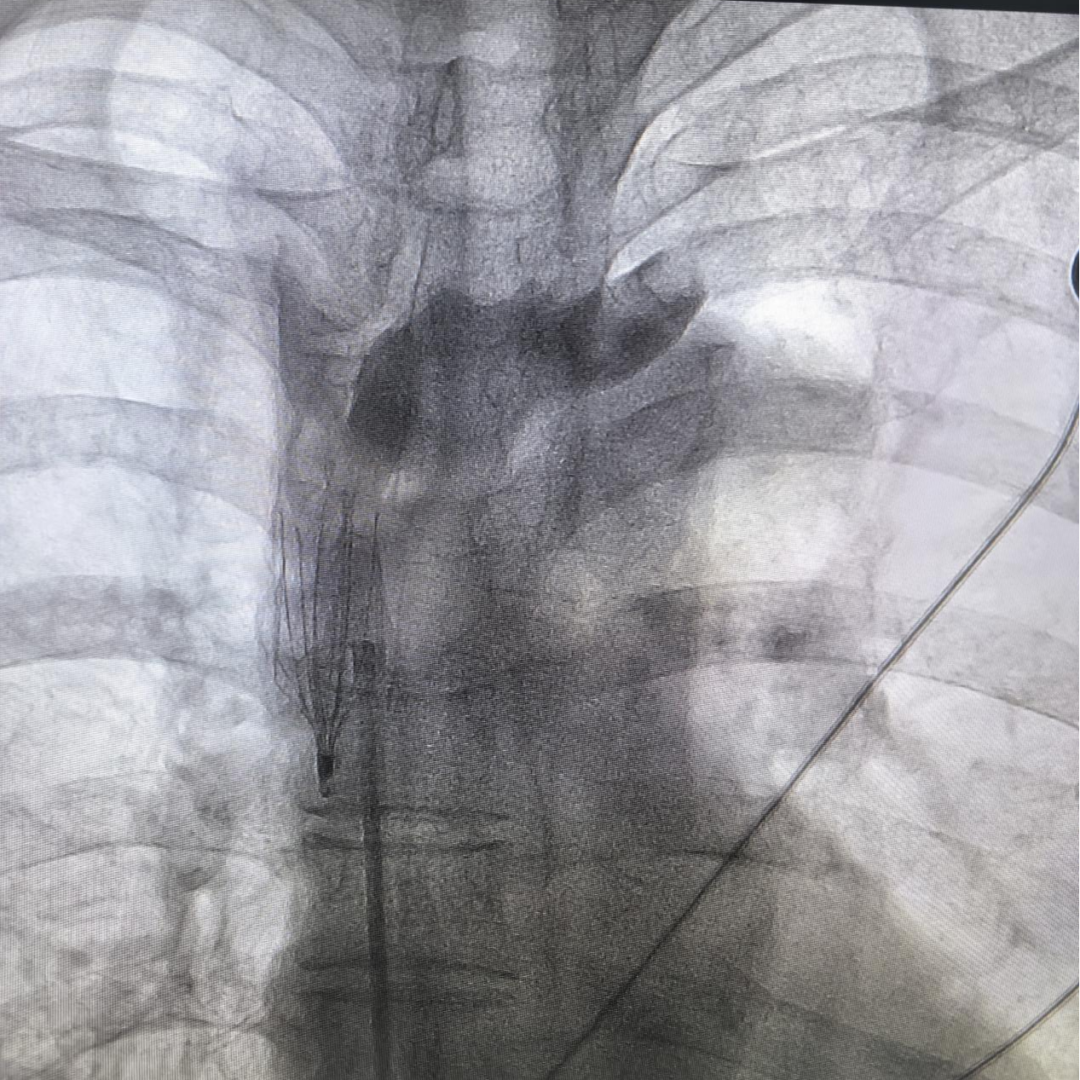

近日,在西京医院介入中心对口帮扶专家王占奎医生的带领下,丹凤县医院普外科团队成功为一名“左上肢深静脉及锁骨下静脉血栓形成”的高危患者,实施了院内首例“上腔静脉滤器植入术”。手术过程顺利,滤器定位精准,术后患者恢复良好,已可正常活动。标志着我院在防治复杂性、特殊性静脉血栓栓塞症(VTE)领域取得了重大技术突破,填补了本地区在该项高难度介入技术上的空白,为周边区域高危血栓患者带来了新的生命希望。

手术当日,在对口帮扶专家王占奎医生及科室主任王超的带领下,在介入中心团队的辛勤配合下,外科团队凭借丰富的经验和精湛的操作技艺,在先进的数字减影血管造影(DSA)设备全程高清引导下,通过患者大腿根部仅针眼大小的穿刺点,将一枚精巧的滤器输送至核心“靶点”——上腔静脉。整个手术过程如行云流水,滤器一次释放成功,位置、形态完美,血流无阻。手术仅耗时约20分钟,患者全程清醒,无痛苦。